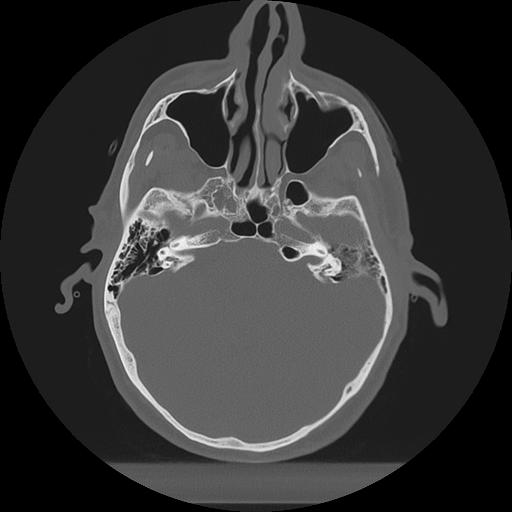

11 HUESO,,Axial,2.0,HUESO,,